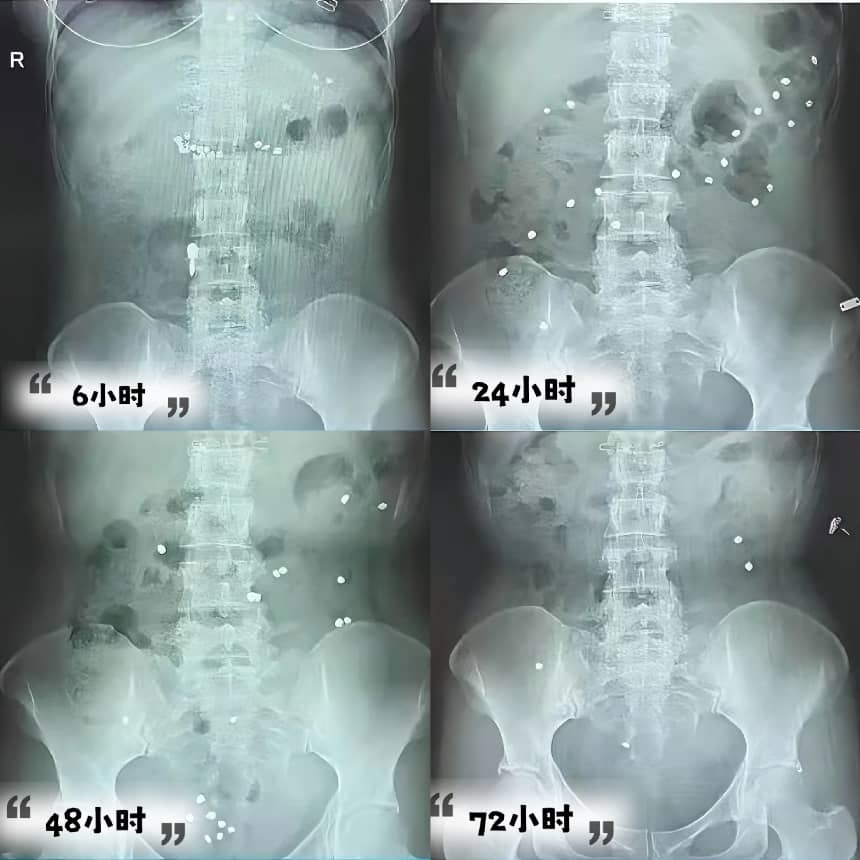

• 拍片时间:服药后6小时、24小时、48小时、72小时分别至一楼放射科拍摄腹部X线片,最后一次拍片结束1小时在自助机领取报告

四、结果分析:肠道“慢不慢”一看便知!

1.正常:48小时残留率≤20%,肠道传输效率满分!

2.慢传输型便秘:48小时残留率>20%,标记物均匀分布于结肠

3.出口梗阻型便秘:48小时残留率>20%,标记物集中于直肠

4.混合型便秘:残留标记物分散在结肠且有集中于直肠或乙状结肠,需进一步检查